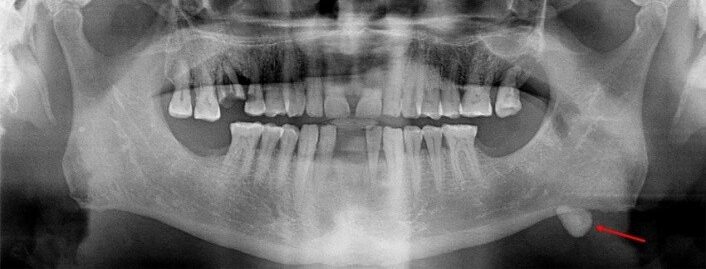

19 / 30

19. (Select ONE correct answer)

What is the most likely diagnosis for the entity shown by the arrow?